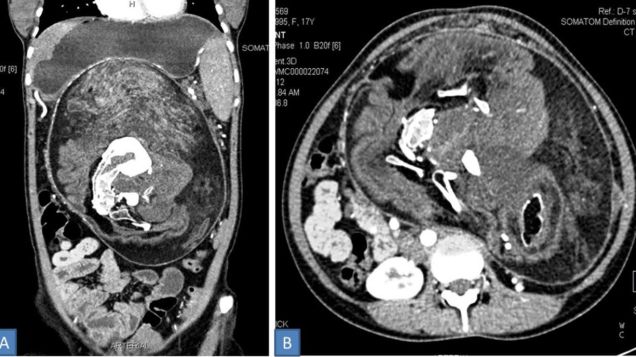

A young woman in India unknowingly lived with one of the rarest and most unsettling medical conditions for nearly two decades, her doctors say. According to a case report out this week, the woman had a sac containing her still-growing “twin” lodged in her abdomen for 17 years. The twin had hair, teeth, and even a…